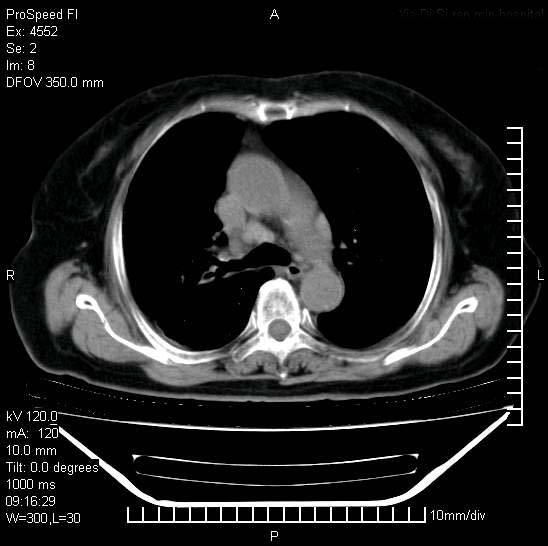

十几年前曾患肺结核,一周前突咳血约100ml,中性粒细胞稍高,诊断两上肺陈旧结核,下肺炎症,给予抗炎治疗,近几日晚上高热,39度,仍咳少量血,4天前ct及今天ct上传。

[face=黑体]8月30日[/face]

支持陈旧性肺结核并两下肺感染,两侧胸腔积液。

考虑1双肺tb灶;右下肺支气管壁增后,建议除外占位 3双侧胸腔积液,

短短几天内,病变范围明显增多扩大,以左侧明显,而且双侧出现胸水,还是考虑感染.

支持  结核ban感染,节段性肺不张,支气管内膜结核可能

短短几天内,病变范围明显增多扩大,以左侧明显,而且双侧出现胸水,我更多考虑左侧中心性肺癌并并阻塞性不张及肺炎,炎症变化也太快了!

继发性结核感染加重。左侧合并有支气管内膜结核。

无论是肿瘤还是炎症4天的时间都发展够快的,并且还在治疗中,如果说是左肺癌那么右肺的病变不好解释,本人更加倾向于炎症,左肺舌叶支气管被痰栓或血凝块堵塞,造成阻塞性肺炎。

1)两肺结核并感染。2)不排除左肺上叶中央型肺癌并阻塞性肺炎、肺不张可能;建议行纤支镜检查。3)右肺门及纵隔淋巴结肿大。4)双侧胸腔积液。

陈旧性肺结核及左下肺不张,咯血后肺部感染,双胸腔积液,高热可能与痰液引流不畅有关。